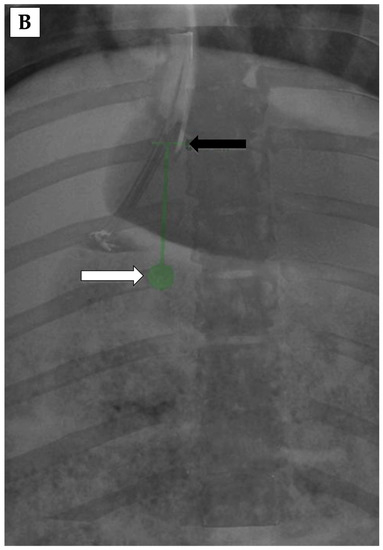

3.4. 3D Angiography-Guided DIPS Using CT/CBCT/Angiography-Fused Images